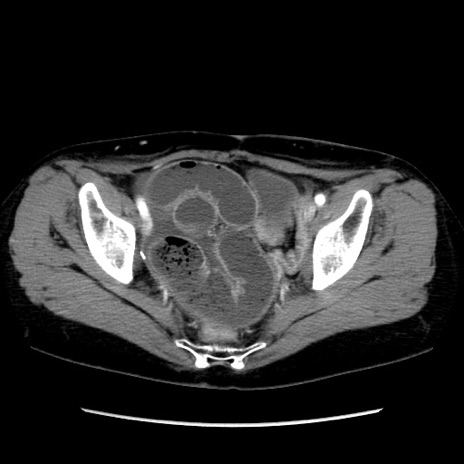

症例32(横断像)

【症例】40歳代 女性

【主訴】上腹部痛、嘔気・嘔吐

【現病歴】約9時間前頃から急に上腹部痛、嘔気、嘔吐が出現。改善しないため救急要請。

【既往歴】子宮頚癌(広汎子宮全摘術、放射線療法)、腸閉塞

【身体所見】腹部:平坦、軟、腸雑音亢進、上腹部を中心に腹部全体に圧痛あり。

【データ】WBC 8400、CRP 0.03